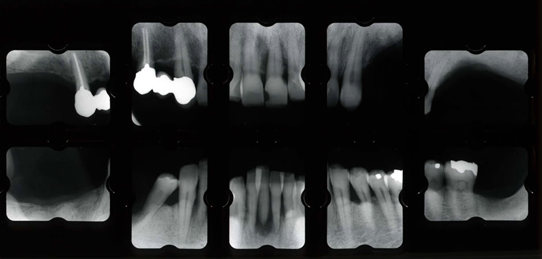

治療前

左右の奥歯がなく前歯だけで噛んでいました。その為に歯周病が進行し前歯が動いてきています。レントゲンで細かく検査すると、残っている歯も歯周病が進行していました。噛み合わせも含めた総合治療が必要でした。

治療中

奥歯をしっかり噛める様にする事が重要です。その為に骨造成後にインプラント治療を行いました。弱ってる前歯は歯周治療や再生治療を行い審美的な問題を解決します。このような細かく繊細な技術が必要な治療には、治療用の仮歯(プロビジョナルレスロレーション)が必須です。